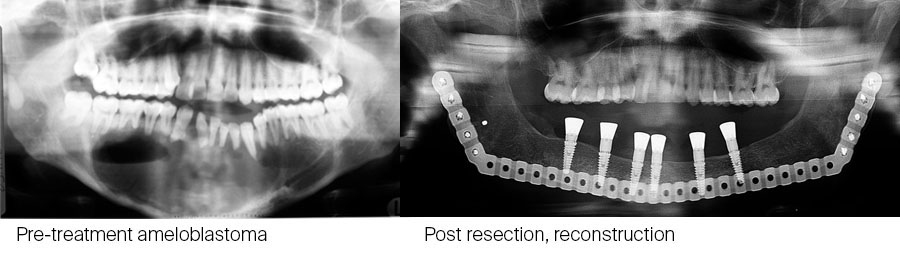

This is particularly useful in children with large defects. An example of such a case illustrated below: CT scan of 10-year-old with large ameloblastoma (A). Panoramic radiograph (B) 13 years post reconstruction and 7 years post implant placement and dental rehabilitation. Patient grafted at age 10 with a composite graft of autologous bone and TGF-β3 loaded onto DBM (demineralized bone matrix).